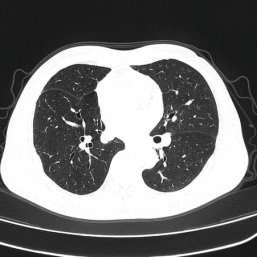

Lung imaging from a traditional X-ray machine

One of the most notable advantages is their ability to provide high-resolution images. They can detect very small anatomical details and abnormalities. For example, in lung cancer screening, CT scan machines can detect nodules as small as a few millimeters, which is unattainable with traditional X-ray machines. These high-resolution images allow doctors to clearly visualize the internal structures of organs, helping in making accurate diagnoses of a wide range of conditions.